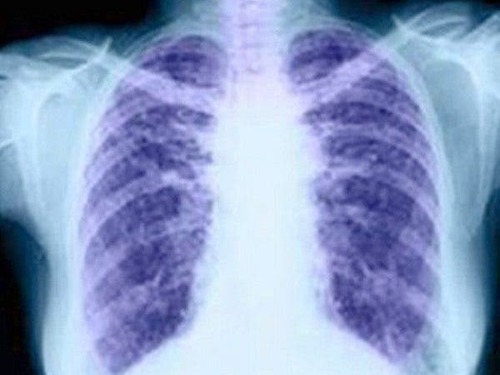

Cáncer de pulmón microcítico: radiografía del tumor más agresivo

El cáncer de pulmón microcítico o de células pequeñas representa al 15% de los tumores de pulmón y se caracteriza por tener una gran agresividad y rápida progresión, por lo que hace más necesario que los tratamientos innovadores, algunos en investigación, lleguen a la práctica clínica